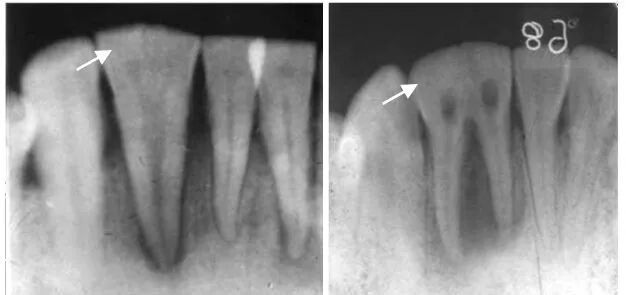

埋伏牙

曲面断层片怎么看正畸【曲面断层片(全景片)】如何解读和查看:牙周?牙体?牙髓?关节?_https://www.jmylbn.com_新闻资讯_第2张

阻生牙

曲面断层片怎么看正畸【曲面断层片(全景片)】如何解读和查看:牙周?牙体?牙髓?关节?_https://www.jmylbn.com_新闻资讯_第19张

拍片注意:阻生牙位臵、方向、本身情况、与邻牙关系、数目及形态、与下牙槽神经管距离和磨牙后间隙大小等。